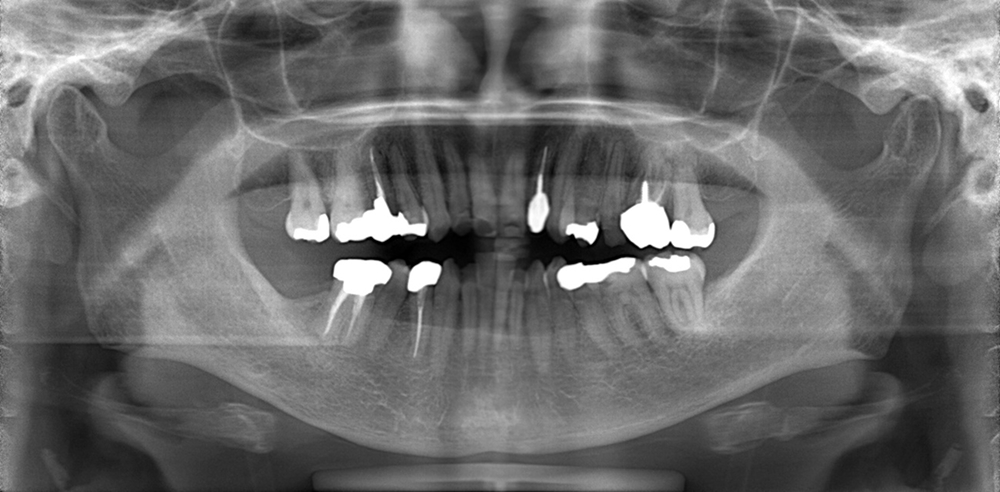

レントゲン検査

歯や歯を支えるあごの骨の状態を調べます。

肉眼でみる情報とは別に確認しにくいムシ歯や歯周病の状態を判断できます。